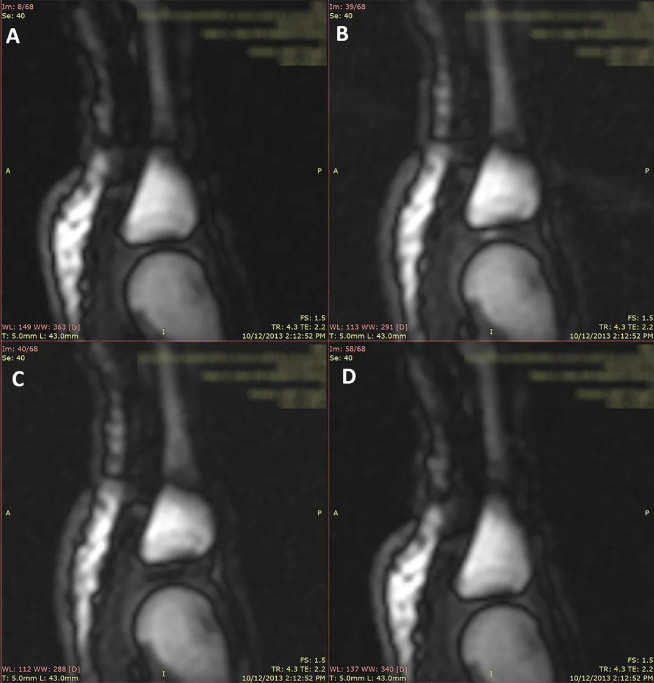

当然,也有一些不同的观点。2005年加拿大的科研团队,动态核磁共振扫描手指关节,他们发现,在手指关节之间充满了滑液,当手指受到牵拉时,滑液也会做出相应变化,这个过程中,滑液中会有气体出现,并在滑液中形成气泡。直到手指发出“咔”的声音,这个气泡都会存在。因此,他们认为掰手指时响声的出现,并不是气泡破裂产生的,而是和关节内空腔形成有关。

关节牵开时,可以看到关节腔里面有黑颜色的空腔形成。